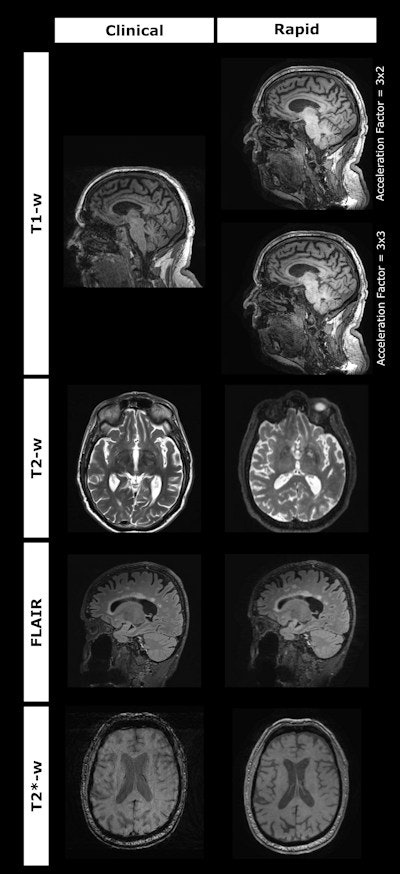

The standard protocol consisted of T1w, T2w, FLAIR and T2*/SWI sequences, while the rapid protocol used Siemens' work-in-progress wave-CAIPI sequences (3D MPRAGE, 3D FLAIR, 3D T2 and 3D T2*).

The study found that the rapid protocol reduced scan time by 66%, from 17 minutes 39 seconds to 5 minutes 20 seconds.